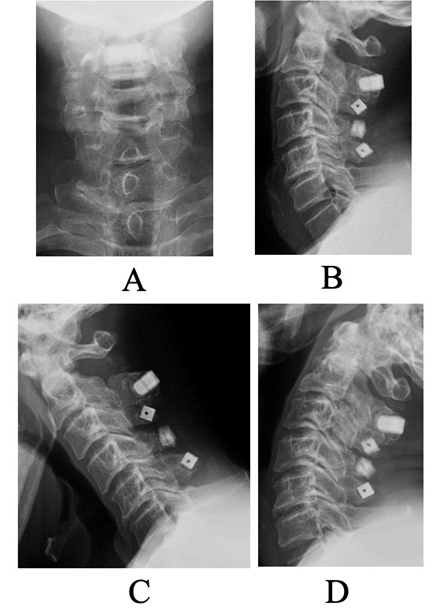

Figure 2: Pre-operative plain lateral radiographs for the current surgery. (a) Anteroposterior view. (b) Neutral lateral view. (c) Flexion view. (d) Extension view. No alignment abnormalities or dynamic instability were observed.

A C2–C5 double-door laminoplasty was performed. Post-operative computed tomography (CT) revealed a narrow lateral gutter at C3 and damage to the inner lamina, but adequate opening of the lamina was achieved, and the spacer was positioned appropriately (Fig. 1). In the current pre-operative plain radiographs, there was no deterioration in alignment, and no evidence of vertebral slippage or intervertebral instability (Fig. 2).